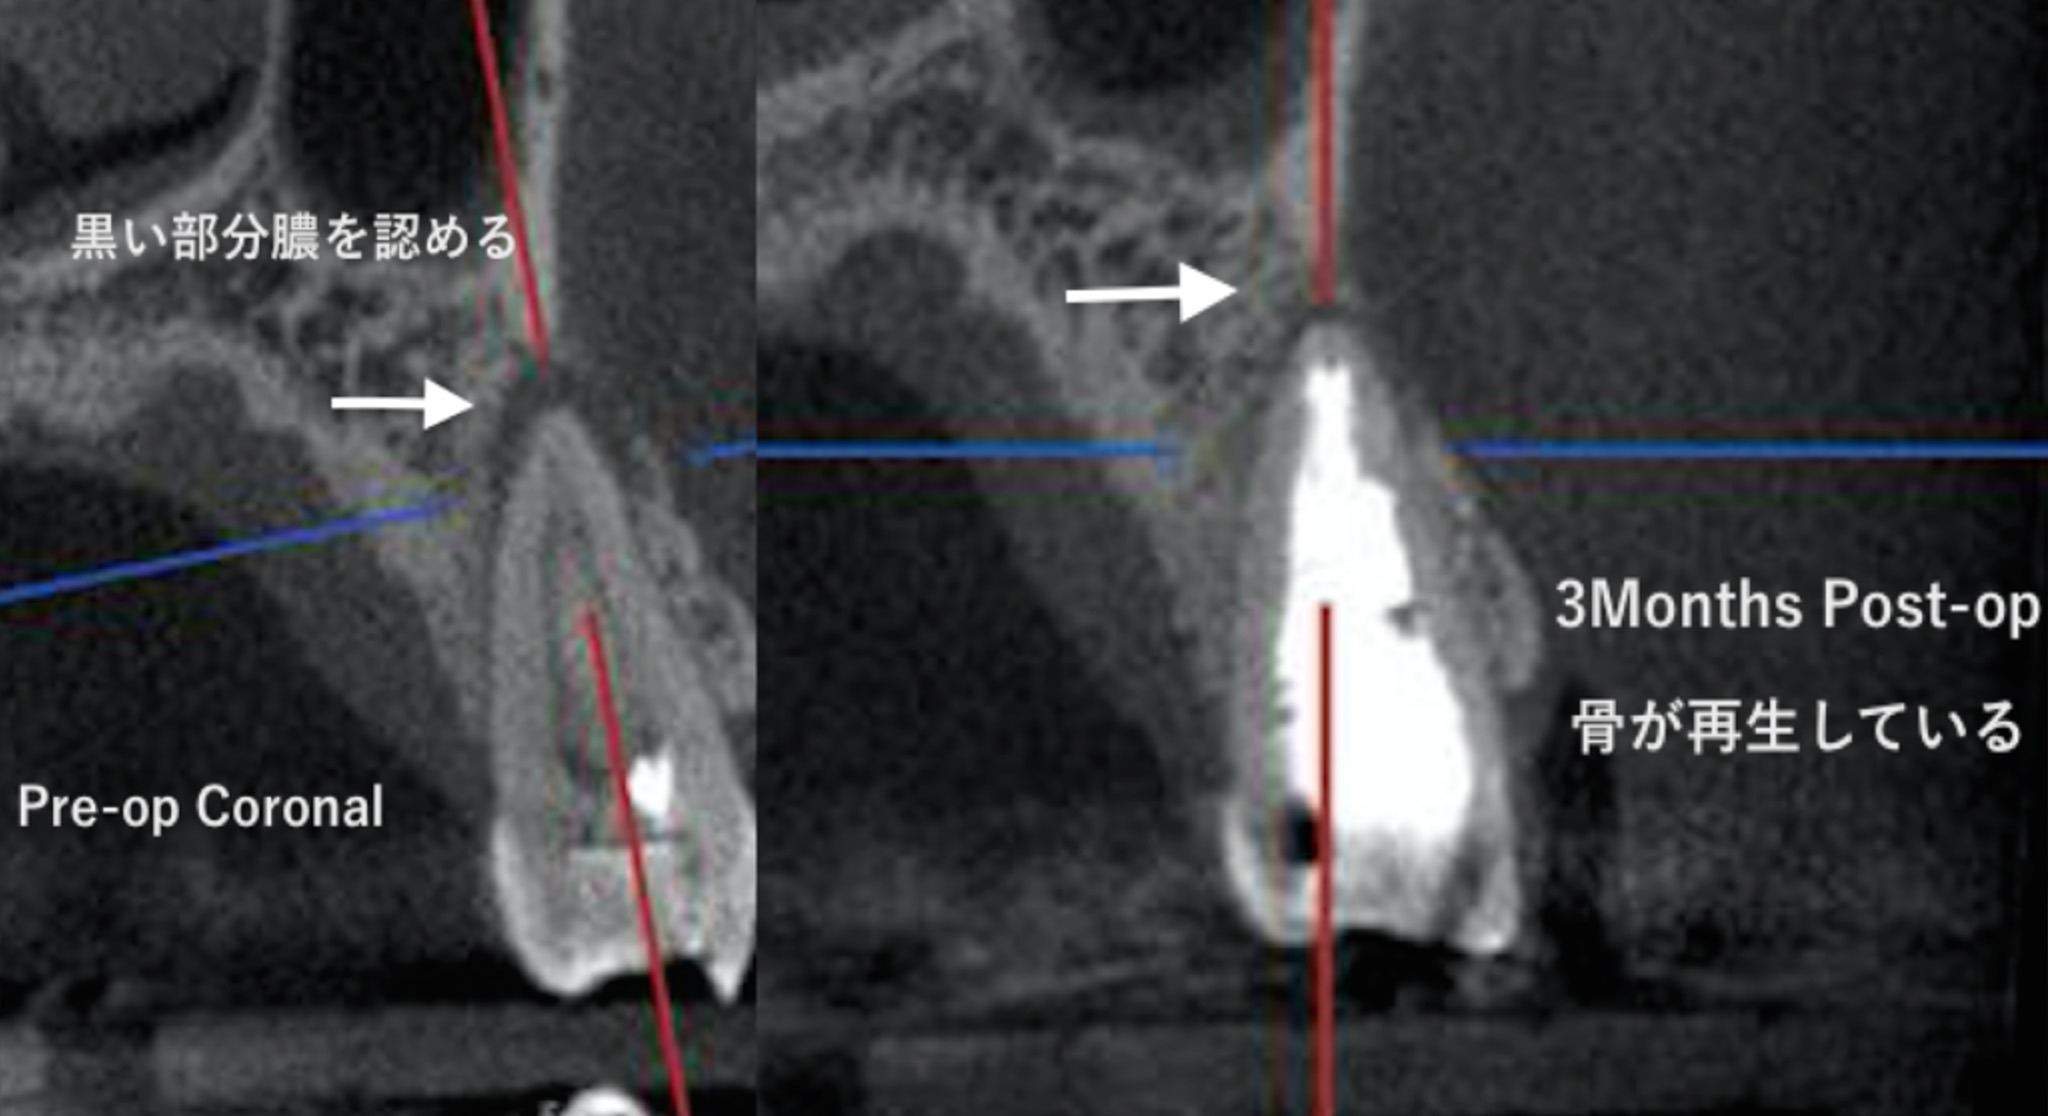

前医から「歯が割れているかもしれない」と診断され抜歯を勧められた。

| 主訴 | 前医から「歯が割れているかもしれない」と診断され抜歯を勧められた。 |

|---|---|

| 治療期間 | 根管治療1時間2回。3か月後CT撮影し治癒を確認後、クラウン修復。 |

| 治療内容 | マイクロスコープとCTを使用した根管治療3か月後に治癒を確認してクラウン修復を行った。 |

| 治療費 | 根管治療:¥121,000円 土台:¥22,000円 仮歯:¥11,000円 クラウン修復:¥154,000円 |

| 治療の リスク |

特になし |